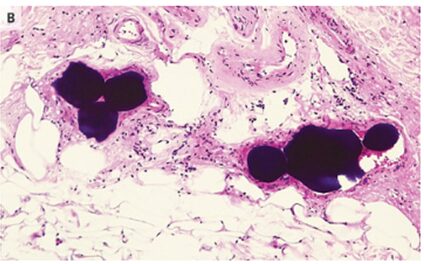

皮膚生検により、HE染色表皮壊死、ケラチノサイトおよびエクリン腺の反応性異型、ならびに緻密な好塩基性物質で構成される円形塞栓による真皮網状小血管の閉塞が明らかになった。